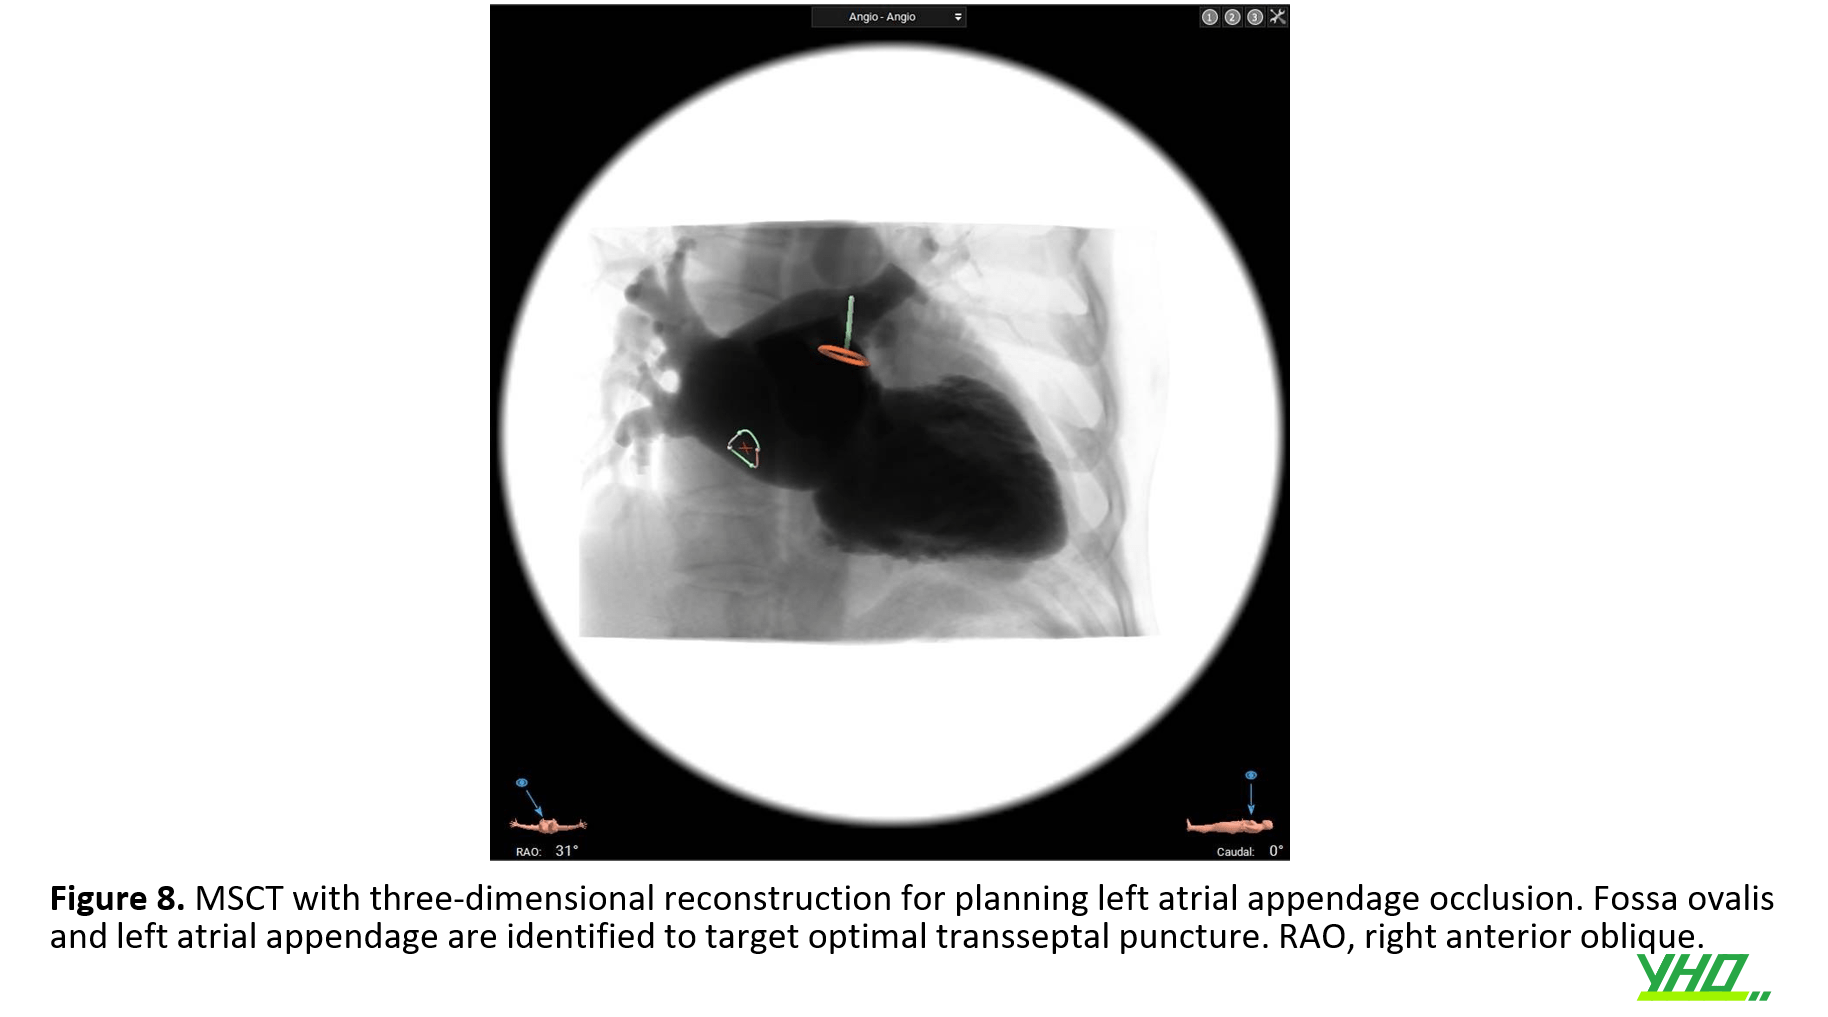

Trong các thủ thuật can thiệp cụ thể như đóng lỗ dò cạnh van hoặc bít LAA, chụp cắt lớp vi tính đa lát cắt tim (MSCT) với tái tạo ba chiều bằng phần mềm chuyên dụng như 3mensio (Pie Medical Imaging, Maastricht, Hà Lan) có thể giúp điều chỉnh xuyên vách liên nhĩ đến cấu trúc tim mục tiêu.(hình 8)